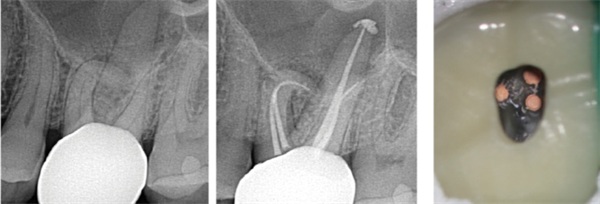

The EdgeOne Blaze Utopia file system is available in four tip sizes (ISO 20 to 45). File selection is based on canal anatomy. R35 or R45 are suitable for large, straight canals such as maxillary anterior teeth and mandibular premolars (Fig. 2). R25 is appropriate for most low- to moderate-difficulty cases, such as maxillary premolars and molars with patent, non-severely curved canals (Fig. 3). R20 is recommended for small, narrow canals and canals with more severe curvature to better follow the original anatomy and minimize procedural errors.

Fig. 2: Pre- and post-operative radiographs of tooth #9 as an example of a large, straight canal prepared with EdgeOne Blaze Utopia R45.